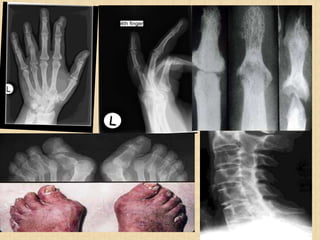

Radiographic Features

• Peri-articular osteopenia

• Uniform symmetric joint space narrowing

• Marginal subchondral erosions

• Joint Subluxation

• Joint destruction

• Collapse

• Ultrasound detects early soft tissue lesions.

• MRI has greatest sensitivity to detect synovitis and

marrow changes.

Asymmetrical joint involvement

Psoriatic arthritis targets PIP and DIP joints of hands and feet

(sausage appearance on examination), nail

pitting, large joints also affected.

Gout MTP great toe, in ch. Affects distal more than proximal

joints, history of acute attacks.

Psoriatic arthritis

• A chronic inflammatory arthritis in association with skin

psoriasis(7%-45%).

• Characterized by osteolysis and bony proliferation.

• Males and females are equally affected.

• Range from mild nondestructive disease to a severely rapid

and destructive arthropathy.

• HLA B27 associated & Seronegative.

• Characterized by synovitis, Enthesitis, dactylitis, spondylitis,

Nail/skin change- 90%

Opera glass hand